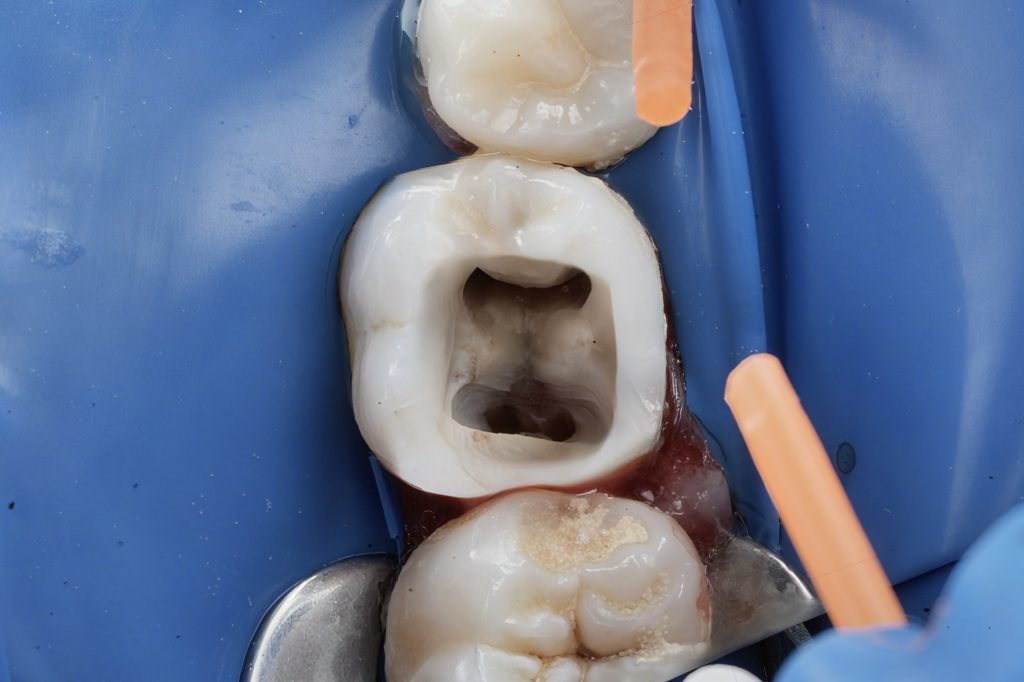

The proximal defect was restored immediately post-obturation.

- Garrison sectional matrix system used for tight proximal contact and contour (Fig 6).

- GC EverX Flow placed as the first 1–2 mm layer to reinforce weakened dentin.

- Incremental build-up completed with Tokuyama Estelite Sigma Quick (A2).

- Fig 6: Class II build-up using Garrison matrix + GC EverX Flow.